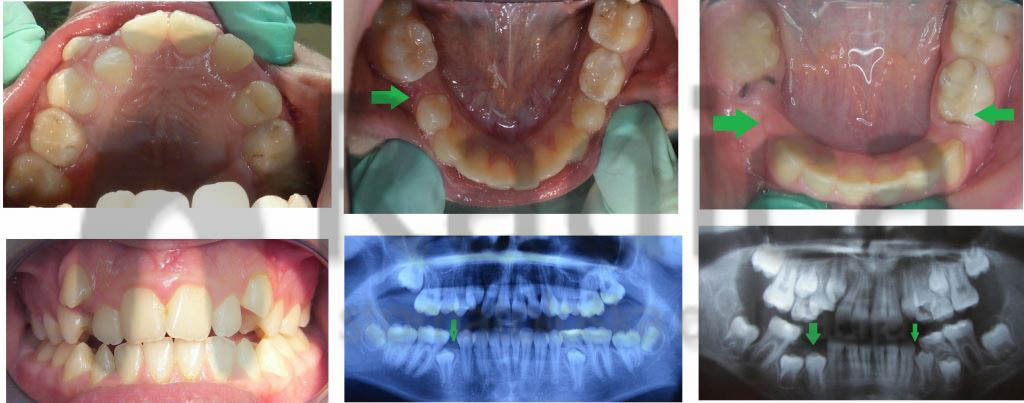

Prerano izgubljen mliječni zub uzrokuje gubitak mjesta za trajnoga nasljednika. Stoga nastaje gužva ili čak neki zubi nemaju gdje niknuti pa ostaju u kosti – nastaje anomalija koju nazivamo sekundarna kompresija.

Najčešće su to zubi koji se zadnji pojavljuju u čeljusti – gornji očnjaci i donji drugi premolari – „petice“.

U sljedećim primjerima su pokazani takvi slučajevi:

U slučaju da ipak dođe do preranog gubitka mliječnih zuba preporučuje se napraviti držače mjesta, transplatinalni i/ili lingvalni lukovi koji sprječavaju pomak „šestica“ i čuvaju mjesto za trajne nasljednike.

Nažalost, najveći broj ortodontskih pacijenata u Hrvatskoj upravo su oni koji su prerano izgubili mliječne i/ili trajne zube jer ih nisu prali niti odlazili stomatologu.

Ortodontske anomalije uzrokovane preranim gubitkom mliječnih zuba i poslije gubitkom trajnih u suvremenom su svijetu rijetka pojava, a kod nas je gotovo svako treće dijete bez trajnih “šestica”.